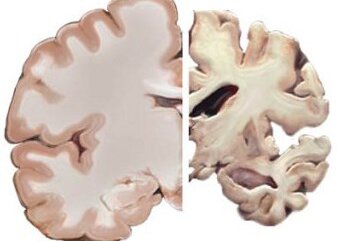

Болезнью Альцгеймера называется неизлечимое нарушение функционирования центральной не Далее...

Рассеянный склероз представляет собой аутоиммунную патологию, при которой собственная Далее...